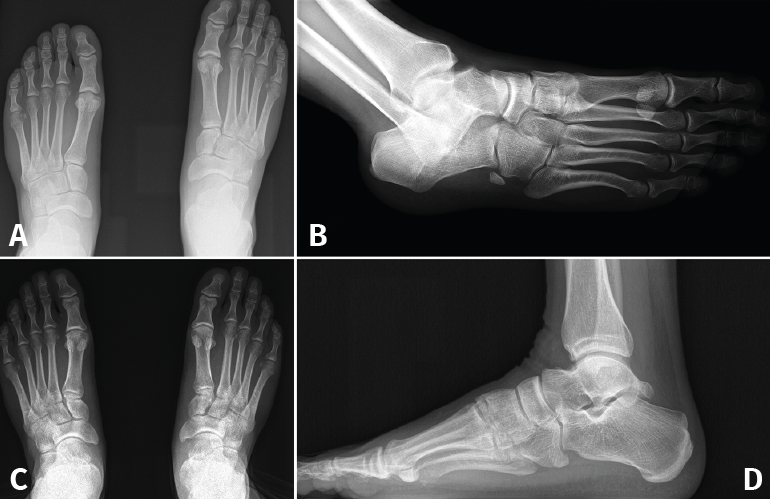

Figura 1. Caso 1. A: radiografía anteroposterior (AP) sin carga; B: radiografía oblicua sin carga; C: radiografía AP con carga con diástasis en la articulación de Lisfranc; D: radiografía lateral con carga.

Se trata de un varón de 32 años diagnosticado de lesión sutil de Lisfranc en urgencias tras un traumatismo deportivo sin especificar el mecanismo. Se realiza estudio radiográfico y tomográfico objetivando diástasis de 2 mm articular en el pie derecho sin lesión ósea (Figuras 1A y 1B). Se decide realizar tratamiento conservador con férula y descarga. Se hace una revisión a las 2 semanas, manteniendo la diástasis previa, pero en la revisión a las 6 semanas se confirma diástasis de 5 mm en la radiografía en carga, por lo que se indica tratamiento quirúrgico (Figuras 1C y 1D).